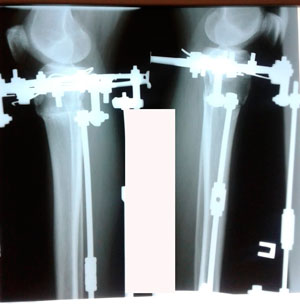

Пациентка - 37 лет.

Диагноз: варусная деформация голеней. Ротация с обеих сторон.